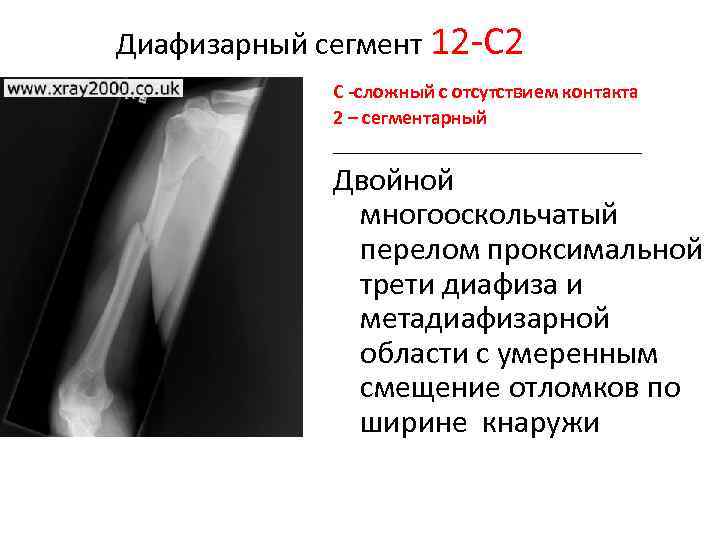

Классификация переломов диафиза бедренной кости: Иллюстрации и информация